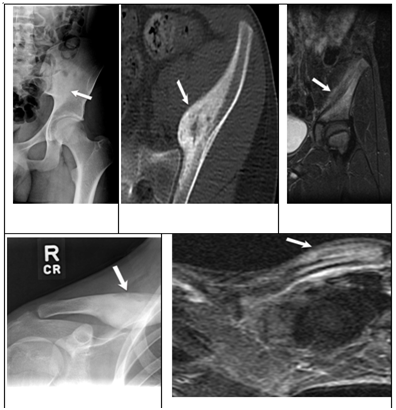

Figure 4 Patient 4 imaging review.

1. Figure 4A: One view X-ray showing chronic thickening and mature periosteal reaction.

2. Figure 4B: Axial T1 post contrast demonstrating bone marrow edema and ongoing maturing periosteitis.

3. Figure 4C: Axial T1 shows cortical thickening and bone marrow edema.

4. Figure 4D: Coronal T1 demonstrating sclerosis and mature periosteal reaction.